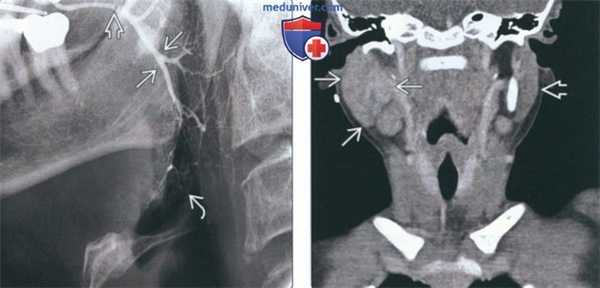

(Слева) На традиционной сиалограмме у пациента с паротидным сиаладенитом определяется легкое расширение протоков (реверсивная архитектура). Терминальные протоки и ацинусы практически не визуализируются. В дистальных отделах протока Стенсена определяется рентгенонегативный сиалолит.

(Справа) На корональной КТ с КУ(реконструкция) у семилетнего ребенка с острым вирусным паротитом определяется избыточное контрастное усиление увеличенной правой околоушной железы. Левая железа не изменена. Абсцессы, лимфаденопатия, конкременты отсутствуют.

2. Рентгенография при воспалении околоушной железы:

• Традиционная или КЛКТ-сиалография:

о «Реверсивная протоковая архитектура»: расширение (а не сужение) проксимальных протоков

о Чередующиеся расширения/стриктуры («связка сосисок») (сиалодохит)

о Скопления контраста за пределами протоков/ацинусов (шаровидная и деструктивная сиалэктазия)

о Показаны при воспалении протоков и сиалолитах (особенно минимально обызвествленных)

о Не показаны для оценки объемного воздействия и при острой инфекции

3. КТ при воспалении околоушной железы:

• КТ без КУ:

о Гиперденсная околоушная железа с неровными краями (бак-териальная/вирусная инфекция)

о Обычно обнаруживаются сиалолиты

• КТ с КУ:

о Острая фаза:

- Диффузное повышение плотности увеличенной околоушной железы (бактериальная/вирусная инфекция)

- Маленькие контрастирующиеся сосуды могут имитировать часто встречающиеся сиалолиты

- Сиалэктазия и изменения протоков вариабельны

- Абсцесс: гиподенсная полость с контрастирующимся «ободком»